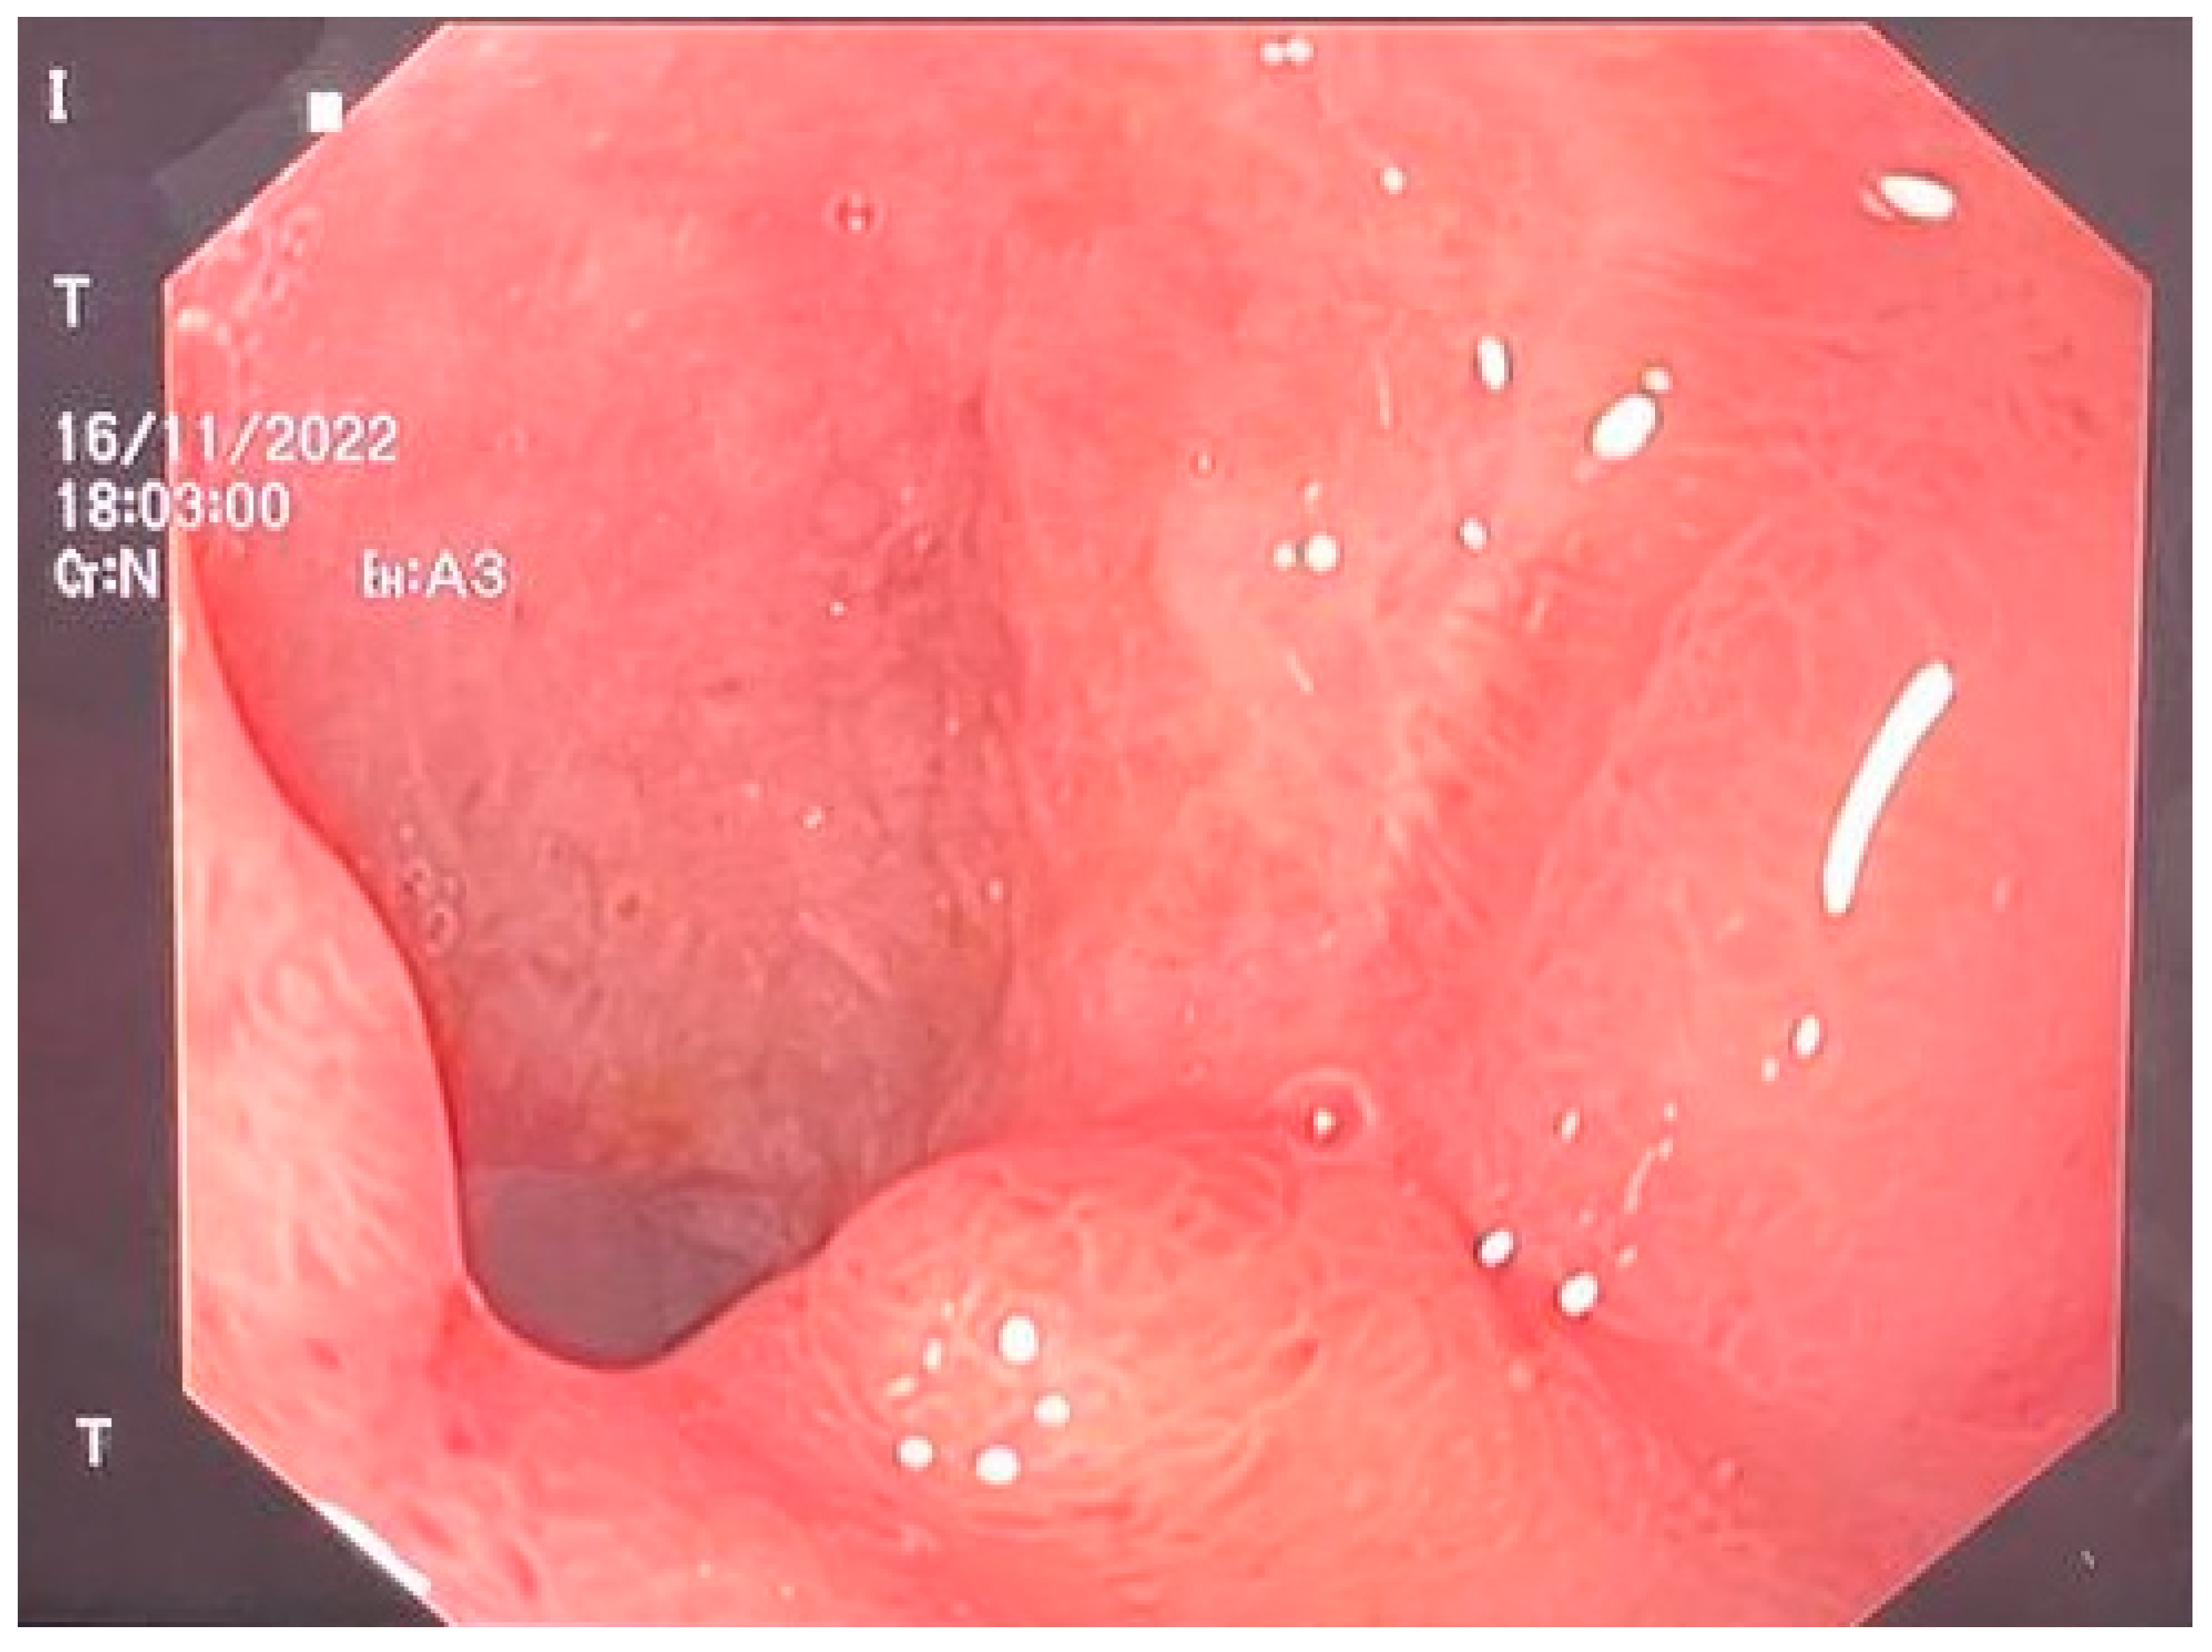

We performed an abdominal-pelvic CT scan, which revealed the closure of the perforation with the absence of extravasation from the gastrointestinal tract of the orally administered contrast. The contrast was present in the jejunum. The right subphrenic collection dimensions were reduced, with mixed air/liquid content at a maximum of 25 mm. At the level of the perforation, anteriorly describes the aspects of a pseudodiverticulum (length 20 mm, permeable lumen 7 mm), which associates with discrete infiltrates of adjacent fat. Bilateral pleural liquid with a thickness of 36 mm on the right and 33 mm on the left was present, with passive atelectasis of the underlying lungs and bilateral basal fibrosis bands [Figure 3].

Figure 3.

Absence of extravasation from the gastrointestinal tract of the contrast substance.